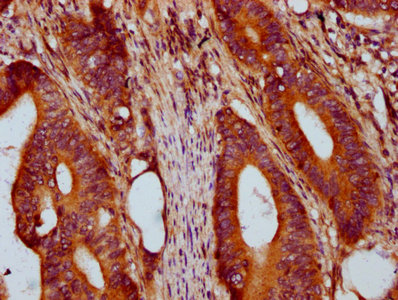

IHC image of CSB-PA882073LA01HU diluted at 1:400 and staining in paraffin-embedded human colon cancer performed on a Leica BondTM system. After dewaxing and hydration, antigen retrieval was mediated by high pressure in a citrate buffer (pH 6.0). Section was blocked with 10% normal goat serum 30min at RT. Then primary antibody (1% BSA) was incubated at 4°C overnight. The primary is detected by a biotinylated secondary antibody and visualized using an HRP conjugated SP system.